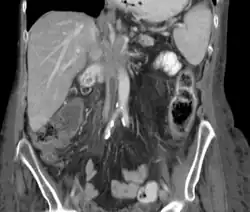

Liczne przerzuty raka trzustki do wątroby

Przerzuty drogą krwionośną pojawiają się głównie w wątrobie i płucach, następnie w nadnerczach, nerkach, kościach, mózgu i skórze[113]. Najczęstszą lokalizacją przerzutów jest wątroba i przerzuty w tej lokalizacji są stwierdzane w 60% przypadków przerzutów odległych[152]. Klinicznie w zaawansowanej chorobie nowotworowej obserwuje się postępujące pogorszenie stanu ogólnego, nasilenie bólu i spadek masy ciała, prowadzi to do kacheksji i ostatecznie do zgonu[153].